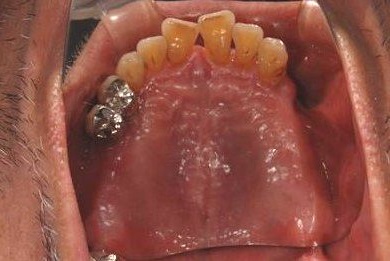

| 性別/年齢 | 男性 / 67歳 | ||||||||||||||||||||||||||||||||

| 主訴 | 欠損部分のインプラント・差し歯治療を希望。 | ||||||||||||||||||||||||||||||||

| 治療内容 | インプラント8本(サイナスリフト、ソケットリフト、GBR)、メタルボンドセラミック8本 | ||||||||||||||||||||||||||||||||

| 治療期間 | 1年5ヶ月 |